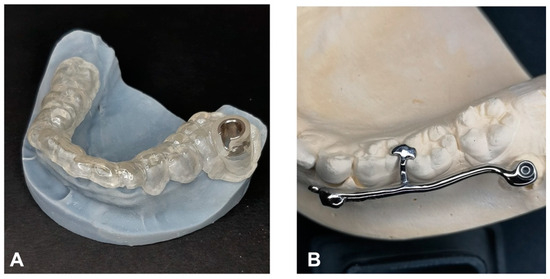

The procedure and potential risks associated with canine disimpaction, with particular emphasis on the risk of root resorption to adjacent elements, were fully explained to the subject and parents and signed informed consent for the publication of images and data was obtained. The disimpaction treatment consisted of a surgical phase of exposure of the impacted canine, with the possible removal of eruptive obstructions, and an orthodontic traction phase performed with a custom-made skeletal and dental anchorage device. The miniscrew insertion sites were planned on 3D images generated by merging CBCT and digital dental model images. The TADmatch 3D module of the Onyxceph3™ software (Image Instruments, Chemnitz, Germany) was used for the computer-guided planning of screw insertion using a surgical guide (Figure 5). A CAD/CAM digital workflow was performed to design the surgical guide and the skeletal anchoring disimpaction device using the Ortho Apps 3D module of the Onyxceph3™ software 3.2.180 Build 492–K2 (Image Instruments, Chemnitz, Germany) (Figure 6). The surgical guides were fabricated using TruPrint 1000 (TRUMPF Homberger S.r.l, Buccinasco, Italy) and the disimpaction device by laser melting technology with cobalt chrome metal powder (Stratasys OrhoDesktop; Stratasys, Rehovot, Israel) (Figure 7).

Figure 7. Customized surgical template (A) and disimpaction device with miniscrews (B) on the 3D-printed digital mandible model.